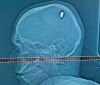

Jovem é atingido por bala perdida na cabeça e só percebe 4 dias depois